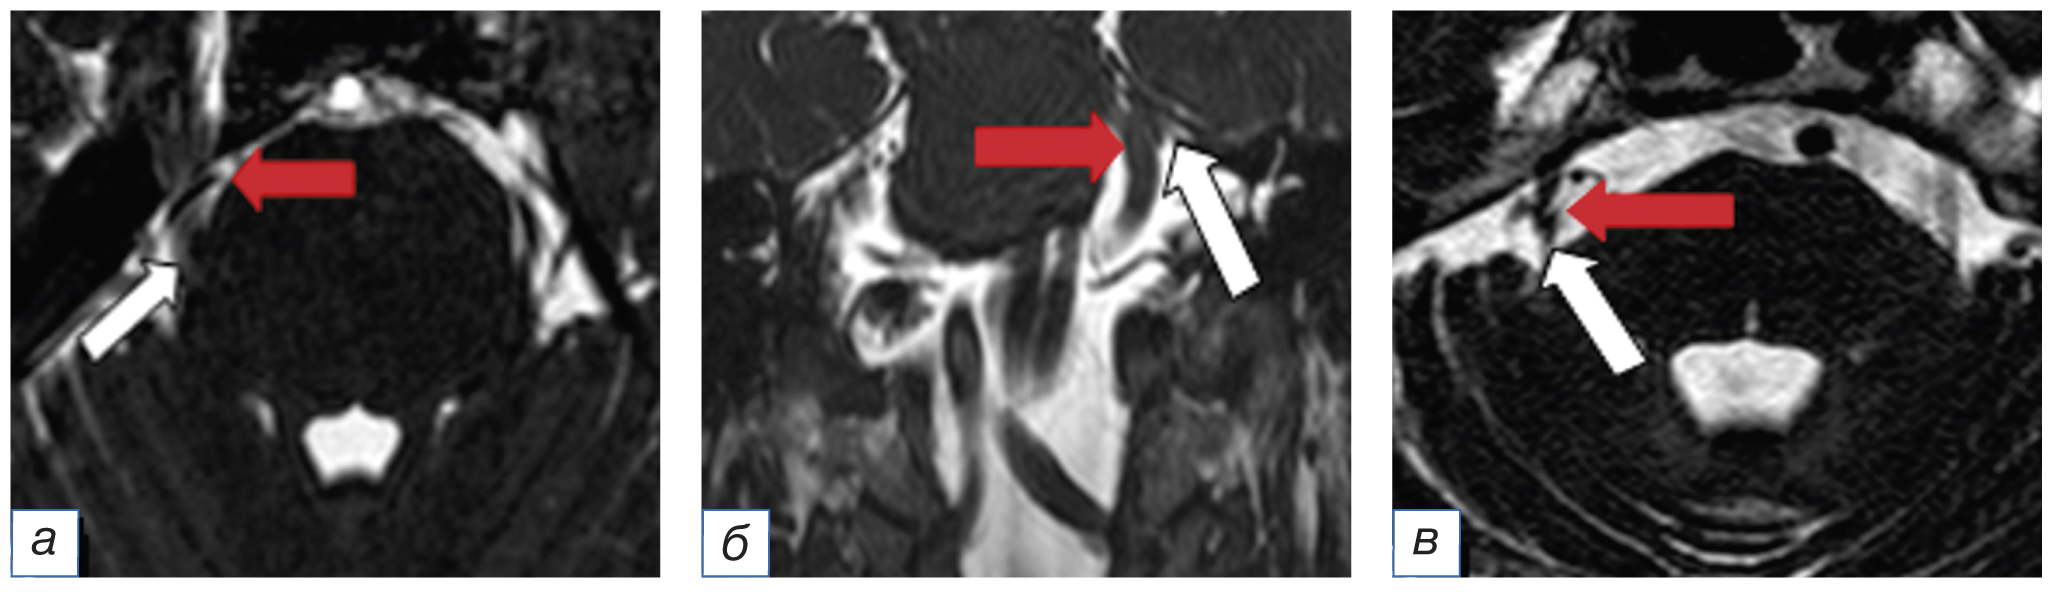

Диагноз подтверждали на основании клинического осмотра и наличия нейроваскулярного конфликта по данным МРТ головного мозга на аппарате мощностью 1,5–3 Тесла в режиме 3D CISS, или FIESTA, или DRIVE. Во всех случаях был выявлен нейроваскулярный конфликт между артерией и/или веной и корешком тройничного нерва. Степень выраженности нейроваскулярного конфликта оценена по шкале M. Sindou и соавт. [12]. Так, I степень компрессии (сосуд контактирует с нервом) выявили у 16 (47%), II степень (сосуд дислоцирует нерв) — у 6 (18%), а III степень (сосуд вызывает видимую атрофию нерва в зоне контакта) — у 12 (35%) пациентов (рис. 1).

Рис. 1. Магнитно-резонансная томография головного мозга в режиме FIESTA в аксиальной (а, б) и фронтальной (в) плоскостях у пациентов с невралгией тройничного нерва в зависимости от степени выраженности нейроваскулярного конфликта по шкале M. Sindou [12]: а — I степень; б — II степень; в — III степень. Стрелкой красного цвета указан сосуд, белого — корешок тройничного нерва. / Fig. 1. Magnetic resonance imaging of the brain in the FIESTA mode in the axial (а, б) and frontal (в) planes in patients with trigeminal neuralgia, depending on the severity of the neurovascular conflict on the M. Sindou scale [12]: а — I degree; б — II degree; в — III degree. The red arrow indicates the blood vessel, the white arrow indicates the root of the trigeminal nerve.